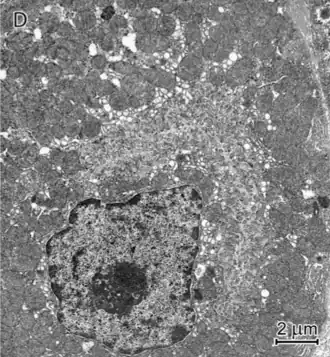

Mediante la microscopía electrónica se pueden observar las características propias de esta célula.

De forma piramidal, el citoplasma de las células parietales está repleto de mitocondrias, con abundantes lisosomas y un sistema tubulovesicular prominente.

Las células parietales son dinámicas en su forma (morfología), porque experimentan una transición entre su estado de reposo y su estado secretor.

El núcleo es esferoidal con nucléolo y cromatina condensada en la periferia. Esta heterocromatina se ve como una delgada cáscara en la membrana nuclear.[6][3]

La célula parietal es particularmente rica en mitocondrias; posee una de las densidades más altas de mitocondrias en el cuerpo humano, alcanza hasta el 40% del volumen total de la célula.